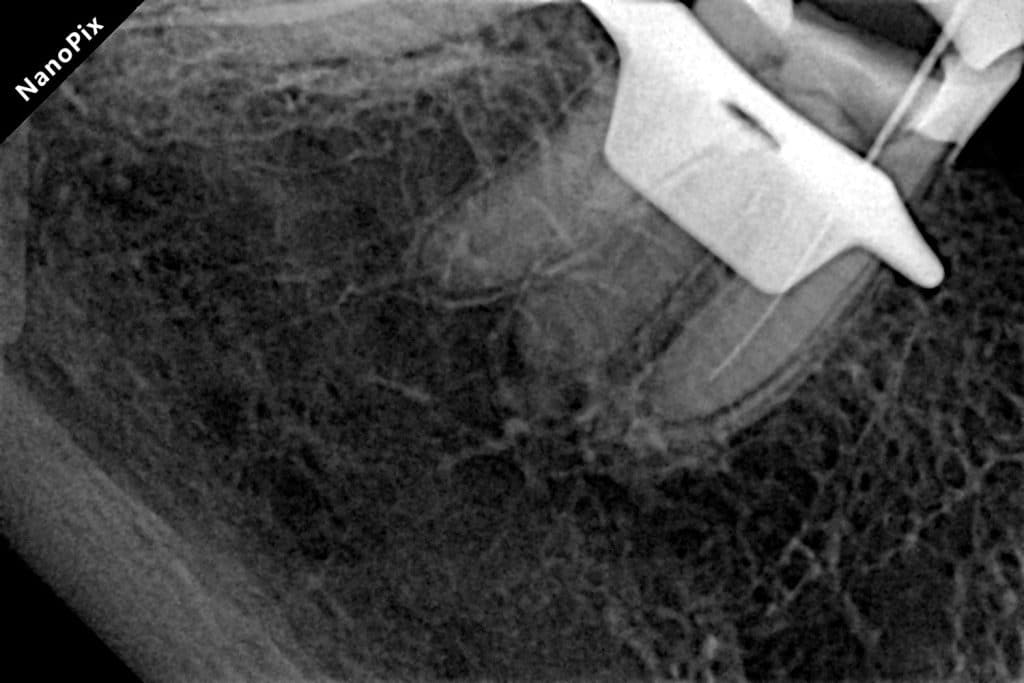

Radix entomolaris

45 years old lady came with symptomatic lower 6

which was treated previously with “pulpotec”

&because of that there was an apical &coronal calcification in the mesiobuccal canal

Unfortunately the last 2 ml of the canal I can’t negotiate it

But thanks to the good irrigation &activation that made the bioceramic sealer close the apex